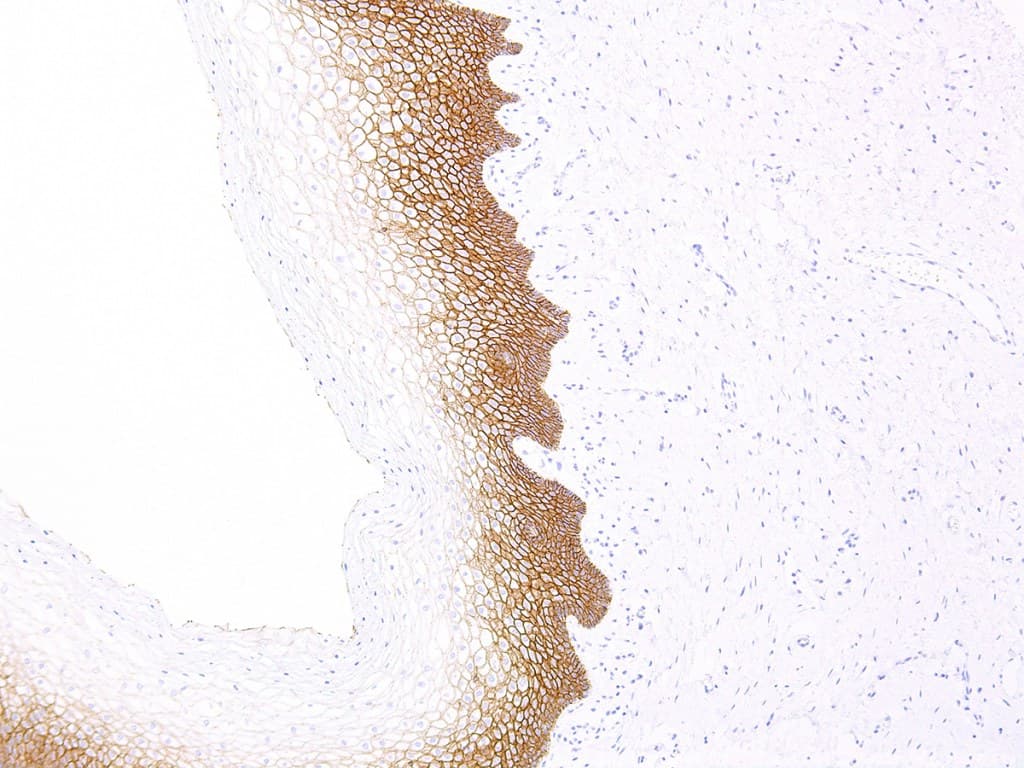

L’E-cadhérine (codée par CDH1) est une protéine d’adhérence cellulaire transmembranaire qui joue un rôle central dans l’intégrité épithéliale.

- Validé pour les tissus FFPE et les plateformes automatisées : de nombreux clones CE/IVD (EP6, HECD-1 et autres) sont optimisés pour les spécimens fixés au formol et inclus en paraffine et pour les colorateurs automatisés utilisés dans les laboratoires cliniques.